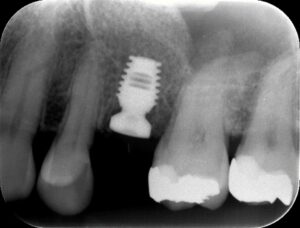

8~3mmの場合は、通常はソケットリフトという方法で、インプラントを埋め込む穴から

骨の素となる骨補填剤を入れて鼻の空洞に骨を作ります。

これでもまだいいほうです。